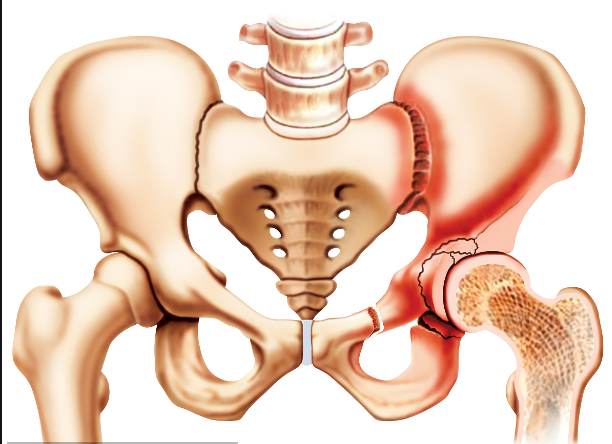

人體的髖關(guān)節(jié)是一個杵臼關(guān)節(jié),就像我們生活中常見的器物杵臼。“杵”就是我們的股骨頭,而“臼”就是指我們的“髖臼”。我們知道,正常情況下,“杵”是嵌在“臼”里面的,有豐富的肌肉保護著,但是,當“臼”的結(jié)構(gòu)不正常時,“杵”在肌肉的作用下就會從“臼”里慢慢跑出來,導致無法正常發(fā)揮作用。近日,瀘州市中醫(yī)院骨三科開展的市屬醫(yī)院首例髖臼周圍截骨術(shù)PAO, 就成功為一名成年患者解決了“杵”與“臼”結(jié)構(gòu)不正常的問題。

“髖臼發(fā)育不良其根源在嬰幼兒時期已經(jīng)存在,由于未及時發(fā)現(xiàn)或治療不徹底而殘留下來 。”瀘州市中醫(yī)院骨三科主任、主任中醫(yī)師李彬介紹,肖女士的髖臼因發(fā)育不良,淺且覆蓋少,因此,造成她的髖臼對位不好。在走路時,因為力學原因,髖關(guān)節(jié)發(fā)生摩擦因而產(chǎn)生強烈的疼痛,如果沒有得到及時的根治性治療,她的病情將慢慢發(fā)展為軟骨炎,最終發(fā)生骨性關(guān)節(jié)炎,影響關(guān)節(jié)功能活動,最后不得進行髖關(guān)節(jié)置換。